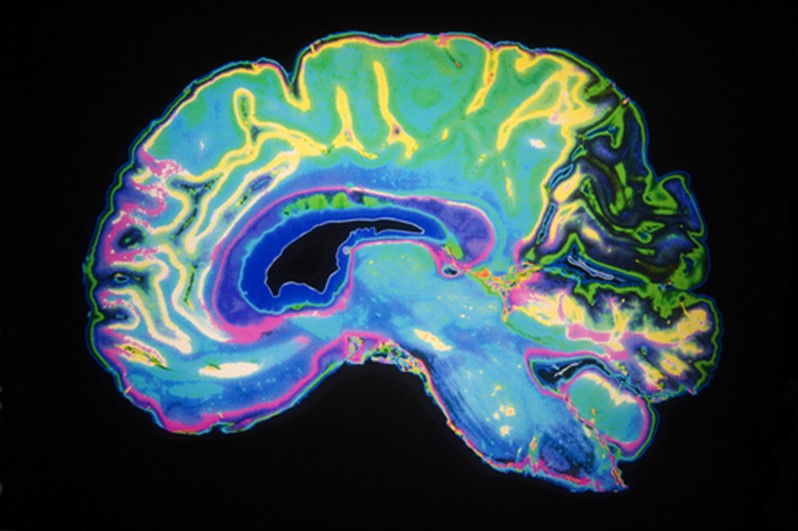

l’heure actuelle, l’IRM (imagerie par résonance magnétique) est la

technique privilégiée dans l’exploration des troubles

psychiatriques.

Elle permet le diagnostic différentiel dans la majorité des

cas et fournit une image de référence qui sera bien utile dans le

suivi d’une maladie organique le cas échéant. Sa précision

anatomique remarquable permet une étude fine des structures

cérébrales et ses performances diagnostiques la rendent

incontournable dans le bilan initial et le suivi de la plupart des

maladies neuropsychiatriques. C’est d’ores et déjà un apport

Par ailleurs, si cette imagerie est d’une précision anatomique

remarquable, elle est également capable d’offrir une vision

fonctionnelle du cerveau : à ce titre, elle a donné une impulsion

majeure dans la recherche en santé mentale. L’IRM dite